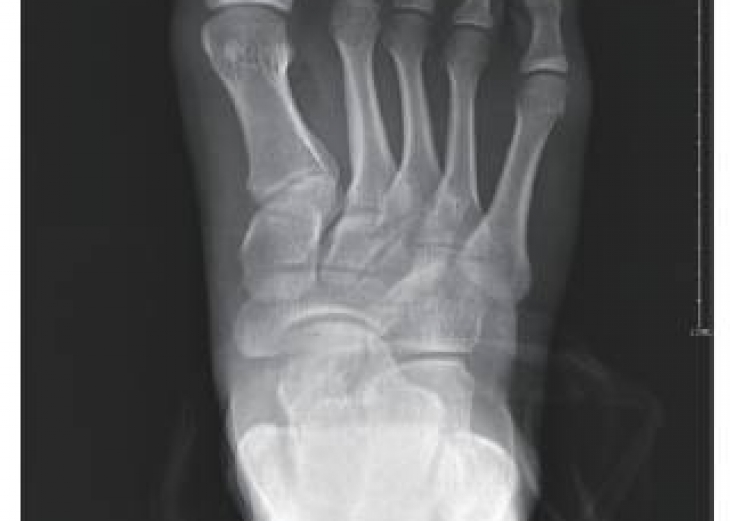

【摘要】目的:国外一些研究表明,特发性马蹄内翻足发病率存在季节型差异。但是,很少有针对于中国特发性马蹄内翻足人群季节发病差异的研究。本研究意在探讨中国东南部地区特发性马蹄内翻足新生...